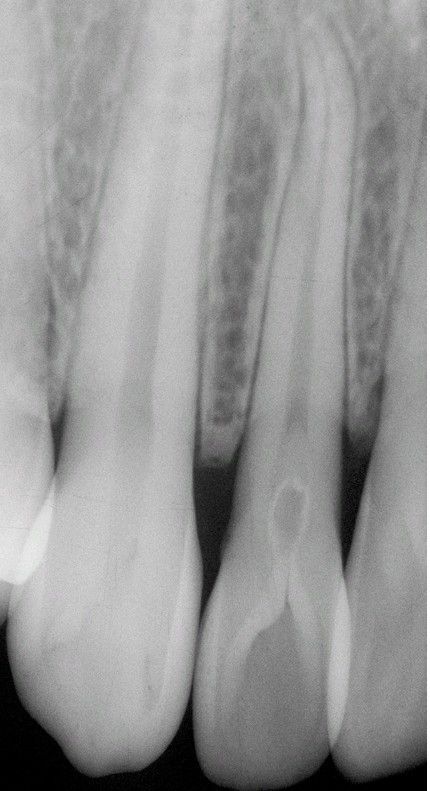

Coronal Dens Invaginatus Type II

. Maxillary lateral incisor exhibiting invagination of the surface enamel that extends below the cementoenamel junction.